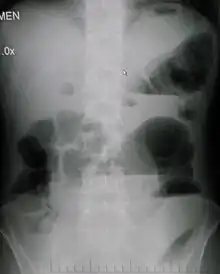

Upright abdominal X-ray of a person with a large bowel obstruction showing multiple air fluid levels and dilated loops of bowel.

Radiological signs of bowel obstruction include bowel distension and the presence of multiple (more than six) gas-fluid levels on supine and erect abdominal radiographs. Ultrasounds may be as useful as CT scanning to make the diagnosis.[13]